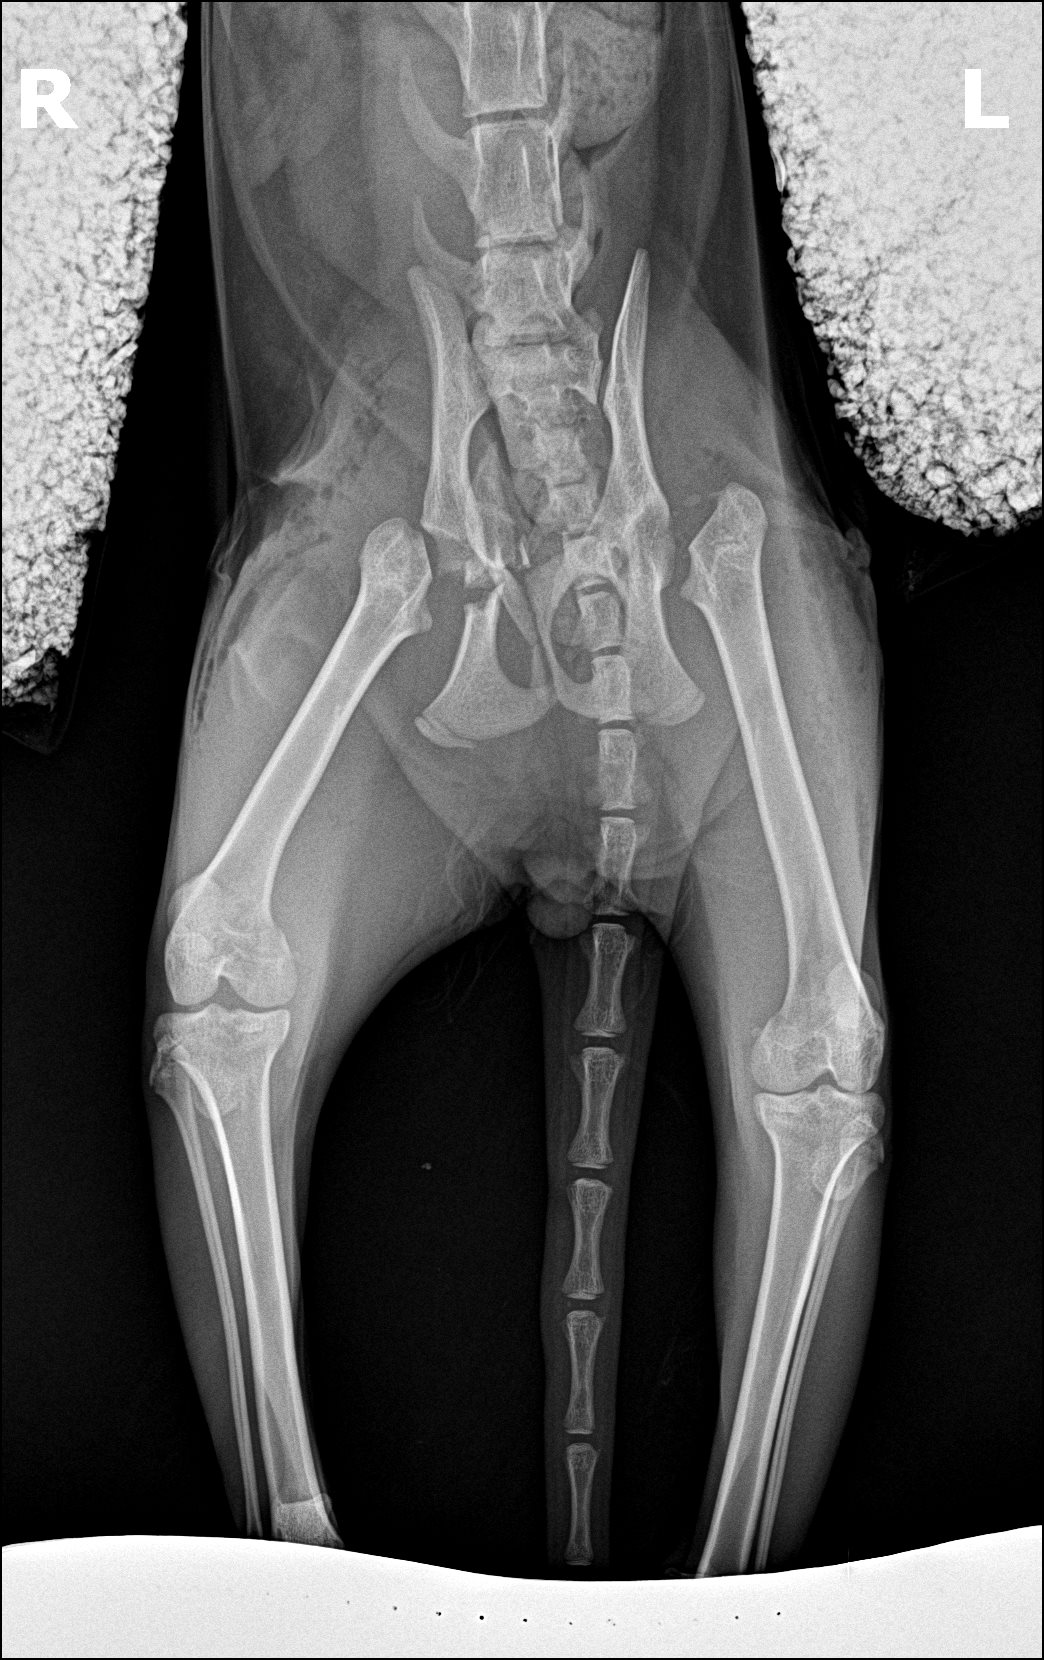

When we took him to the vet because of back leg issues, we were shocked to hear that one hip was broken and the other was dislocated. It couldn’t be put back into place.”

Puff preop X rays

“We figured he would need both sides done as soon as we saw the X-rays, we were definitely concerned if he would even be able to make it through the surgery with his other issues. He had been on cortisone for an extended period of time for his eye issues. He also briefly had a heart murmur. We were worried that, after ending the cortisone, that the healing process would be too difficult for his tiny 6 pound body.”